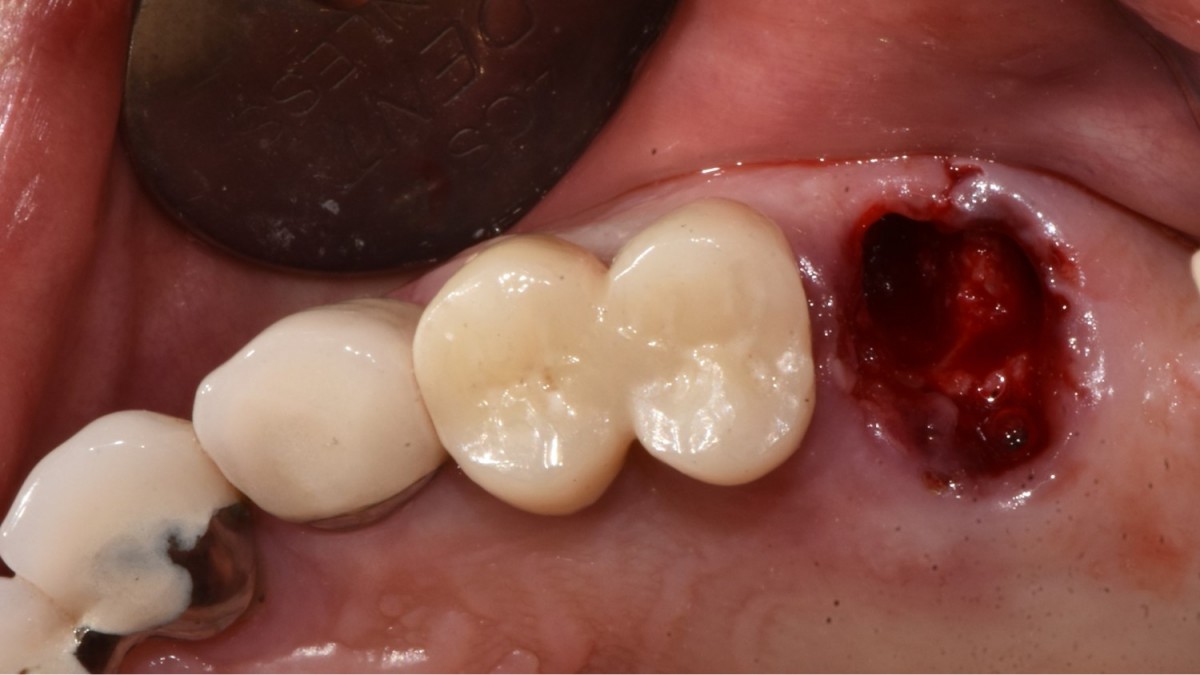

A 57-year-old male patient recently underwent

implant restoration on the maxillary right molar. This time, he is scheduled to

proceed with the left molars. (ARUM implant system)

▲HA was inserted into the membrane with a hole in the middle and then inserted into the place where the Direction Pin was pulled out